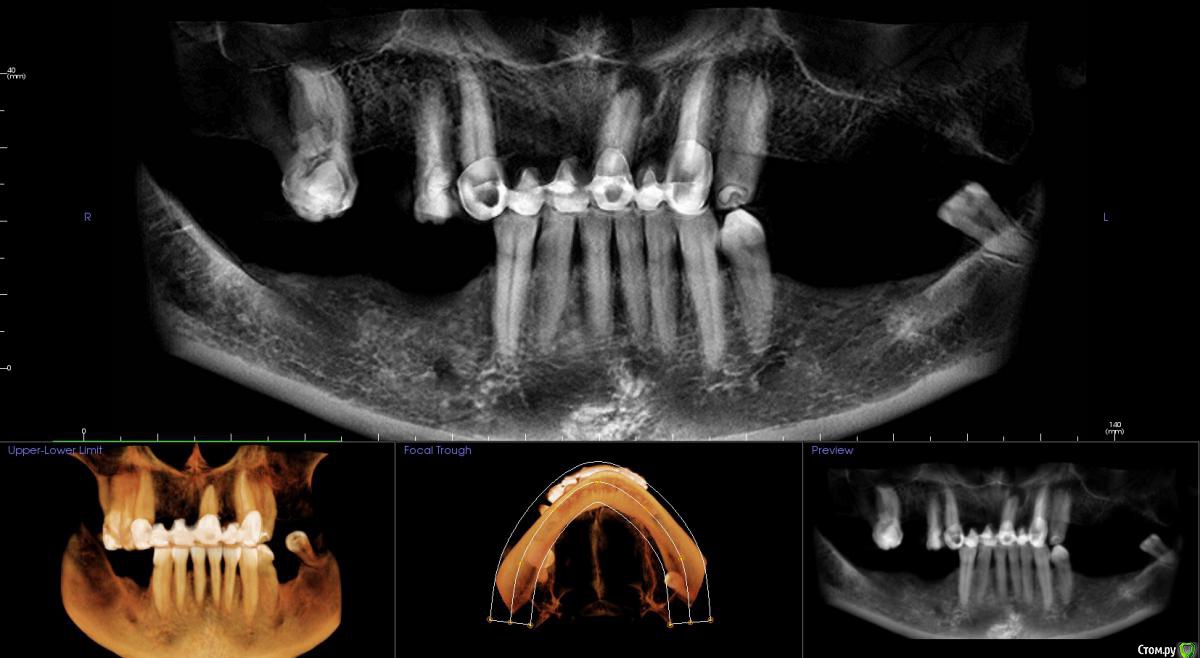

kamranchick Опубликовано 17 февраля, 2015 Поделиться Опубликовано 17 февраля, 2015 Добрый вечер.Имеется следующая проблемаПациент обратлся с жалобами в области отсутствия жевательных зубов, планируется имплантация.Вопросы такого плана, в области 3 сегмента думаю сделать расщепление гребня, установка имплантов 3,75/8 и аугментация костью Ostebiol Gen-Os, мембрана.В области 4 сегмента больше сомнения, планируется титановая сетка +аугментация, либо расщепление опять же, планирую разделить восстановление и имплантауию на 2 этапа в 4 сегментеКакие будут комментарии? Ссылка на комментарий

Shuvalov Опубликовано 17 марта, 2015 Поделиться Опубликовано 17 марта, 2015 Добрый вечер.Имеется следующая проблемаПациент обратлся с жалобами в области отсутствия жевательных зубов, планируется имплантация.Вопросы такого плана, в области 3 сегмента думаю сделать расщепление гребня, установка имплантов 3,75/8 и аугментация костью Ostebiol Gen-Os, мембрана.В области 4 сегмента больше сомнения, планируется титановая сетка +аугментация, либо расщепление опять же, планирую разделить восстановление и имплантауию на 2 этапа в 4 сегментеКакие будут комментарии?Думаю Mane прав И получите прогнозируемый результат! Без сетки! Сосиска рулит Ссылка на комментарий